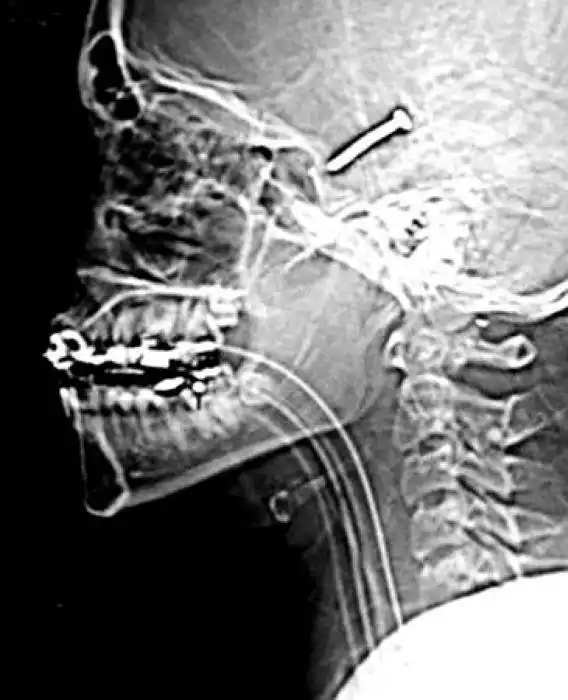

Необычные предметы в теле людей на рентгеновских снимках

На рентгеновских снимках людей порой можно обнаружить самые необычные предметы, которые находятся в их теле.

Человечество явно с гвоздями не дружит!!! Что не снимок то гвоздь в башке!